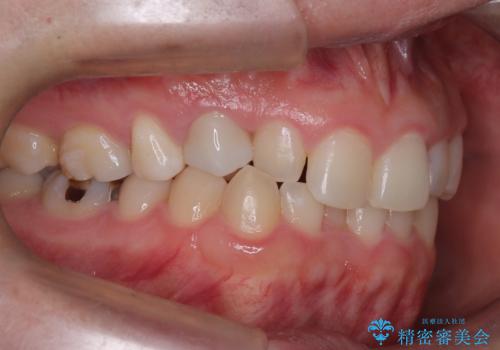

- 下の歯のがたつき(叢生)、真ん中(正中)が右にずれていることを主訴に来院されました。右上前から3番目の永久歯が埋まっている(埋伏)していることから正中は可能な限り合わせることをゴールとしてマウスピースでの矯正治療を選択しました。

今回の矯正治療では、透明なマウスピース型の装置インビザラインを使用しました。がたつきをとるため、安全性が確保できる範囲で歯と歯の間を少し削り必要なスペースを確保しました。